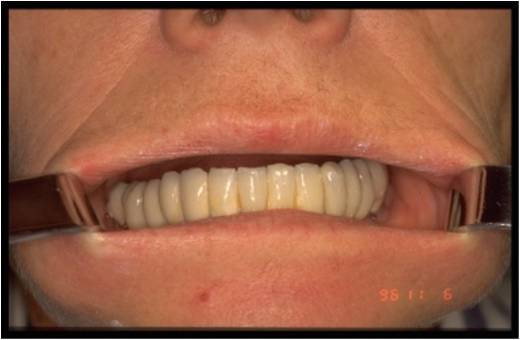

Celle ci a étté posée par voie linguale et de façon totalement endostée ( 6 ans de recul )

Le blocage primaire est assuré par les vis d ostéosynthèse